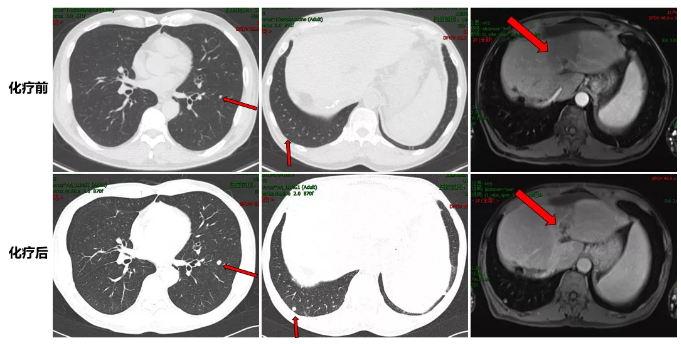

MRI复查结果:疗效评价PR(靶病灶缩小32%)。

化疗前后病灶变化情况